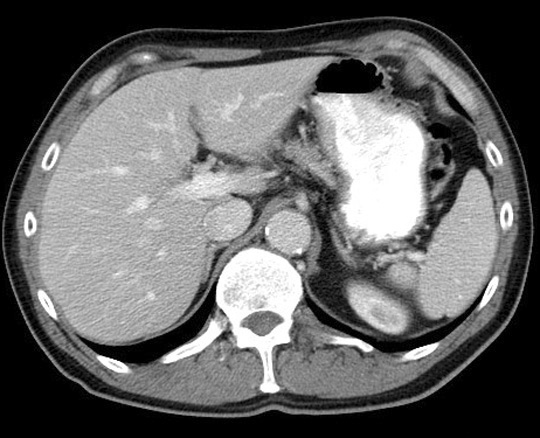

Portal Vein. Click the image for labeling.